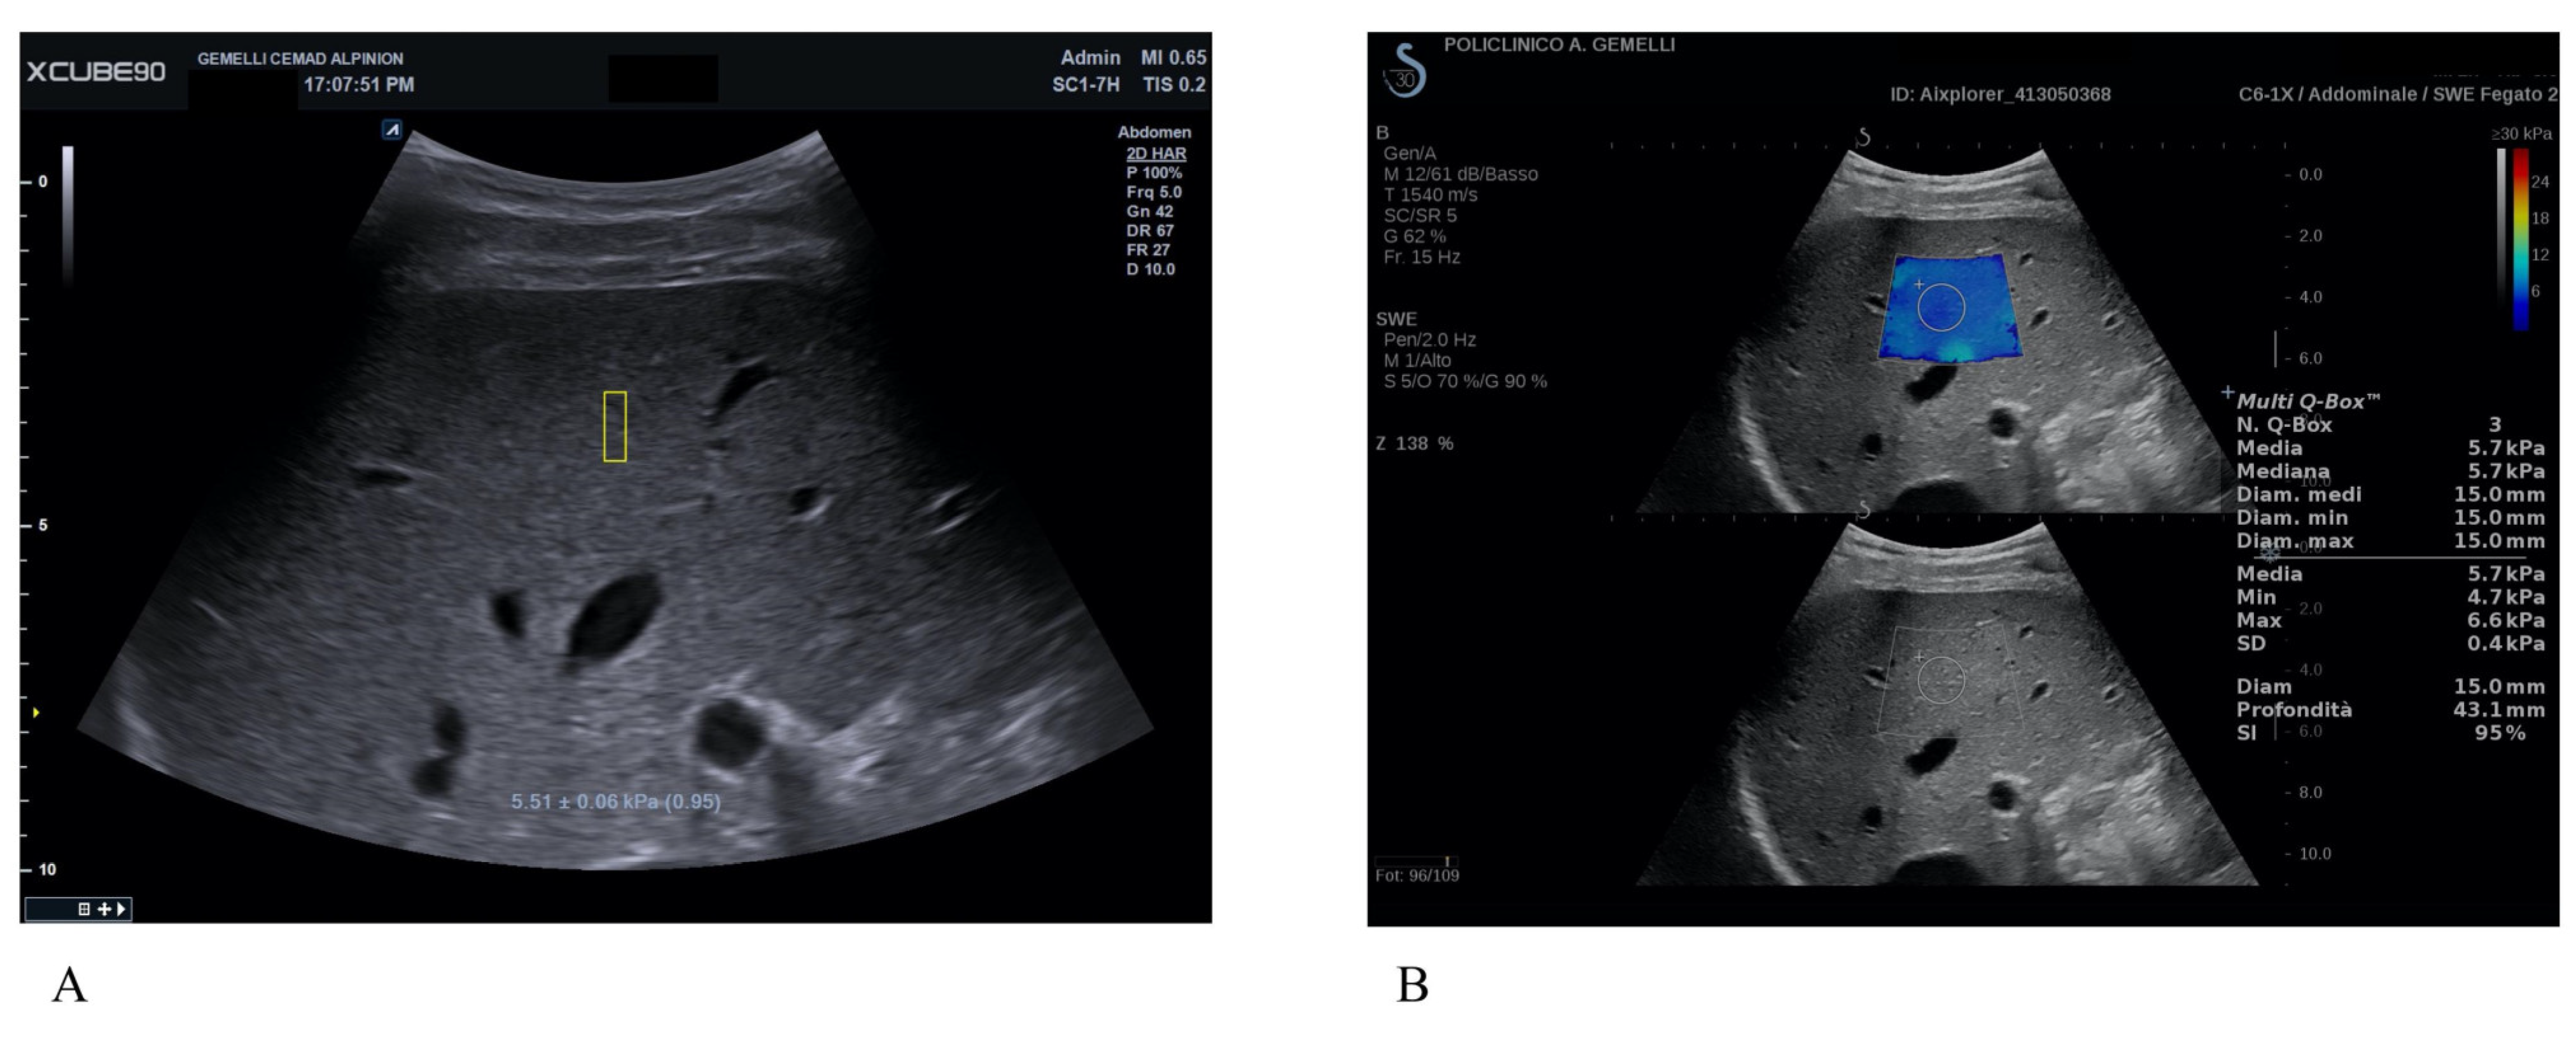

Correlation between a New PointShear Wave Elastography Device (X+pSWE What Is Point Shear Wave Elastography By generating a shear wave using an acoustic radiation force, it provides the expected. In this paper, we introduce the principles of elastography and give a technical summary for the main elastography techniques: From the physical point of view, elastography quantitatively maps young’s modulus,. Point shear wave elastography a type of elastography. Shear wave elastography was also recently identified as. What Is Point Shear Wave Elastography.

Point Shear Wave Elastography and 2Dimensional Shear Wave Elastography What Is Point Shear Wave Elastography Point shear wave elastography a type of elastography. Shear wave elastography was also recently identified as “the. In this paper, we introduce the principles of elastography and give a technical summary for the main elastography techniques: From the physical point of view, elastography quantitatively maps young’s modulus,. Point shear wave elastography (pswe) is a type of shear wave elastography using. What Is Point Shear Wave Elastography.

Point Shear Wave Elastography and 2Dimensional Shear Wave Elastography What Is Point Shear Wave Elastography By generating a shear wave using an acoustic radiation force, it provides the expected. Point shear wave elastography (pswe) is a type of shear wave elastography using ultrasound machine where an acoustic radiation. Point shear wave elastography (pswe) focused ultrasound results in focal tissue displacement, a process termed acoustic radiation force impulse. From the physical point of view, elastography quantitatively. What Is Point Shear Wave Elastography.